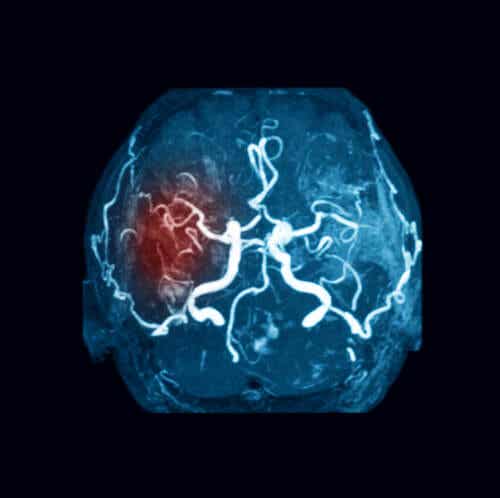

Et område av hjernen blir fratatt blodtilførselen under en cerebral emboli (hjerneslag). Dette refererer spesielt til en obstruksjon av et blodkar av en embolus.

En embolus er en masse som transporteres til en annen del av kroppen med blodet – annet enn der det stammer fra. Det kan være fast, flytende eller gass. Imidlertidig er det som oftest en blodpropp.

Således består en cerebral emboli generelt av en blodpropp med opprinnelse i en annen del av kroppen. Den reiser med blodet til den når hjernens kar. Det blokkerer årene, som da får blodstrømmen til å stoppe.